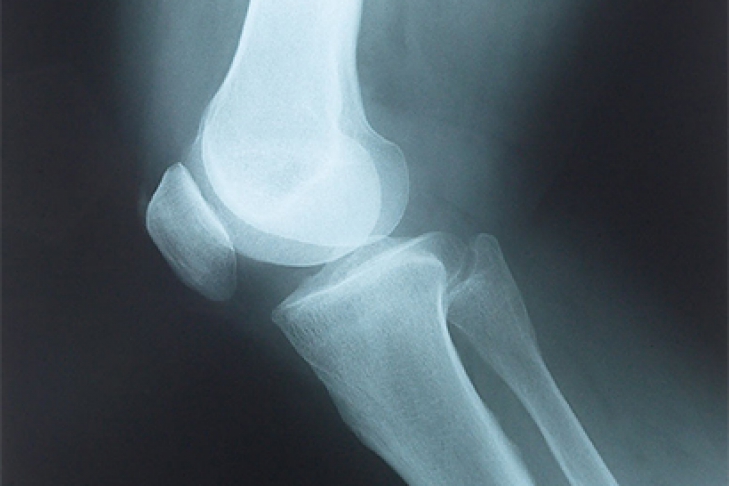

Как и при любой травме коленного сустава для постановки правильного диагноза выполняется рентгенография, на которой-то и можно увидеть перелом. Обычно рентгенографию выполняют в прямой и боковой проекциях, а для диагностики вертикальных переломов выполняют еще и осевую (аксиальную, или Merchant) проекцию.

Прямая (слева) и боковая (справа) проекции, на которых виден горизонтальный перелом надколенника со смещением отломков. Осевая проекция. Вертикальный перелом. Обратите внимание на возникшую в результате смещения ступеньку на скользящей поверхности надколенника.

Осевая проекция. Вертикальный перелом. Обратите внимание на возникшую в результате смещения ступеньку на скользящей поверхности надколенника.Иногда для более точного диагноза могут потребоваться компьютерная и/или магнитно-резонансная томография, но, в подавляющем большинстве случаев, достаточно рентгенографии.

Внешние признаки перелома надколенника имеют ряд характерных особенностей, тем не менее для уточнения диагноза обязательно проводятся рентгенологические исследования. Рентгенологически перелом надколенника особенно хорошо виден на боковом снимке, но в некоторых случаях необходим снимок и в прямой проекции (нога стоит прямо).

Рентгеновские снимки коленной поверхности и профиля будут выполняться систематически. Осевой вид шаровых шарниров в сгибании при 30 ° часто бывает невозможным из-за боли. Эта минимальная рентгенографическая оценка позволяет подтвердить диагноз, указать тип перелома и искать связанные поражения в колене.

Для подтверждения диагноза необходимо выполнить рентгеновские снимки в двух проекциях, иногда требуется выполнение аксиальной проекции, особенно при вертикальных переломах. Обычно, перелом надколенника хорошо виден на рентгеновских снимках.